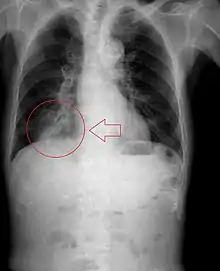

In healthy people, aspiration of small quantities of material is common and rarely results in disease or injury. People with significant underlying disease or injury are at greater risk for developing respiratory complications following pulmonary aspiration, especially hospitalized patients, because of certain factors such as depressed level of consciousness and impaired airway defenses (gag reflex and respiratory tract antimicrobial defense system). The lumen of the right main bronchus is more vertical and slightly wider than that of the left, so aspirated material is more likely to end up in this bronchus or one of its subsequent bifurcations.

The location of abscesses caused by aspiration depends on the position one is in. If one is sitting or standing up, the aspirate ends up in the posterior basal segment of the right lower lobe. If one is on one's back, it goes to the superior segment of the right lower lobe. If one is lying on the right side, it goes to the posterior segment of the right upper lobe, or the posterior basal segment of the right upper lobe. If one is lying on the left, it goes to the lingula.